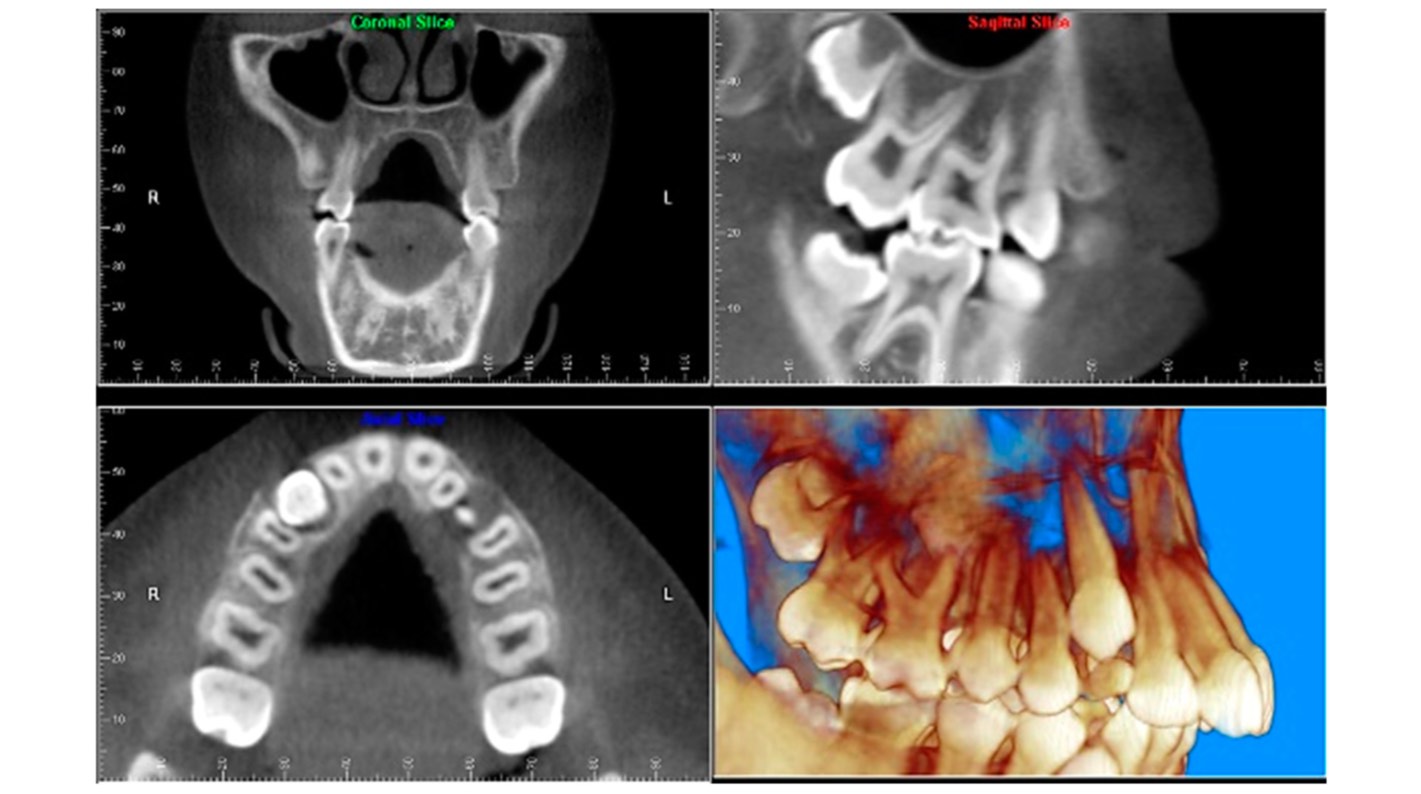

If your field of work is endodontics, a CBCT scanner can provide the axial, coronal and sagittal view that you can't achieve with conventional radiology, although conventional radiology is certainly more practical and suitable for the most common endodontic procedures. CBCT has a great advantage in eliminating or reducing the overlapping of structures, for example, for:

Visualising root canal anatomy: if you use a CBCT scanner with a limited FOV you can more accurately recognise root canals and provide more accurate measurements of root angulations.

Identifying periapical pathology: with a CBCT scanner you could obtain greater sensitivity in the diagnosis of experimental periapical lesions, however, we must not forget that artefacts from restorative materials could hinder the diagnosis.

Identification of tooth fractures: the CBCT scanner outperforms conventional radiology in the diagnosis of tooth fractures because unless the beam is oriented so that it passes through the fracture plane, it is not possible to separate the fragments on an intraoral radiograph. Again, this diagnosis on CBCT may be impaired by artefacts.

Analysis of the internal and external root reabsorption process: with your CBCT scanner you can not only detect the exact location, but also determine the extent of the reabsorption and the communication with the periodontal ligament space.